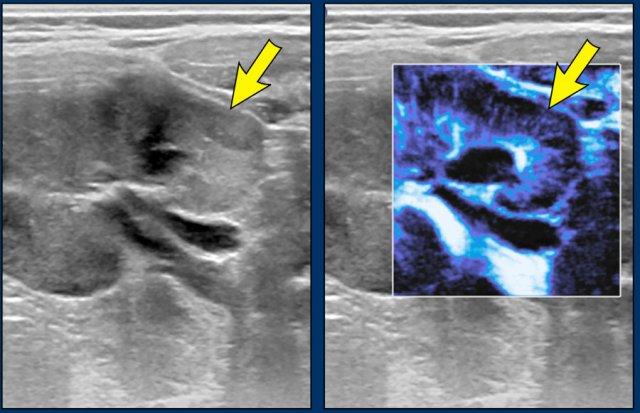

Hình ảnh

Bé trai hai tuổi có u Wilms ở thận trái và nephroblastomatosis hai bên. Trên hình ảnh màu vi dòng chảy, vùng tổn thương có tưới máu kém hơn so với mô thận bình thường.

Trên MRI, nephroblastomatosis được quan sát rõ nhất trên các chuỗi xung sau tiêm thuốc tương phản từ và chuỗi xung khuếch tán (DWI).

Các hình ảnh MRI của cùng bệnh nhân cho thấy tình trạng giảm tưới máu của mô bệnh lý và hạn chế khuếch tán mạnh với giá trị ADC thấp.

Bệnh nhân được điều trị hóa trị liệu tiền phẫu, sau đó khối u ở bên trái được cắt bỏ qua phẫu thuật cắt thận bán phần. Nephroblastomatosis lan tỏa được điều trị bằng phác đồ hóa trị AV (Actinomycin D và Vincristin) hàng tháng trong một năm.